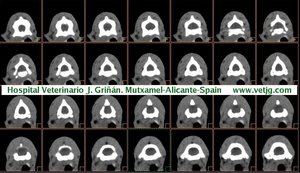

imágenes de TC en el gato | |||||||||||

Tomografía computarizada helicoidal |